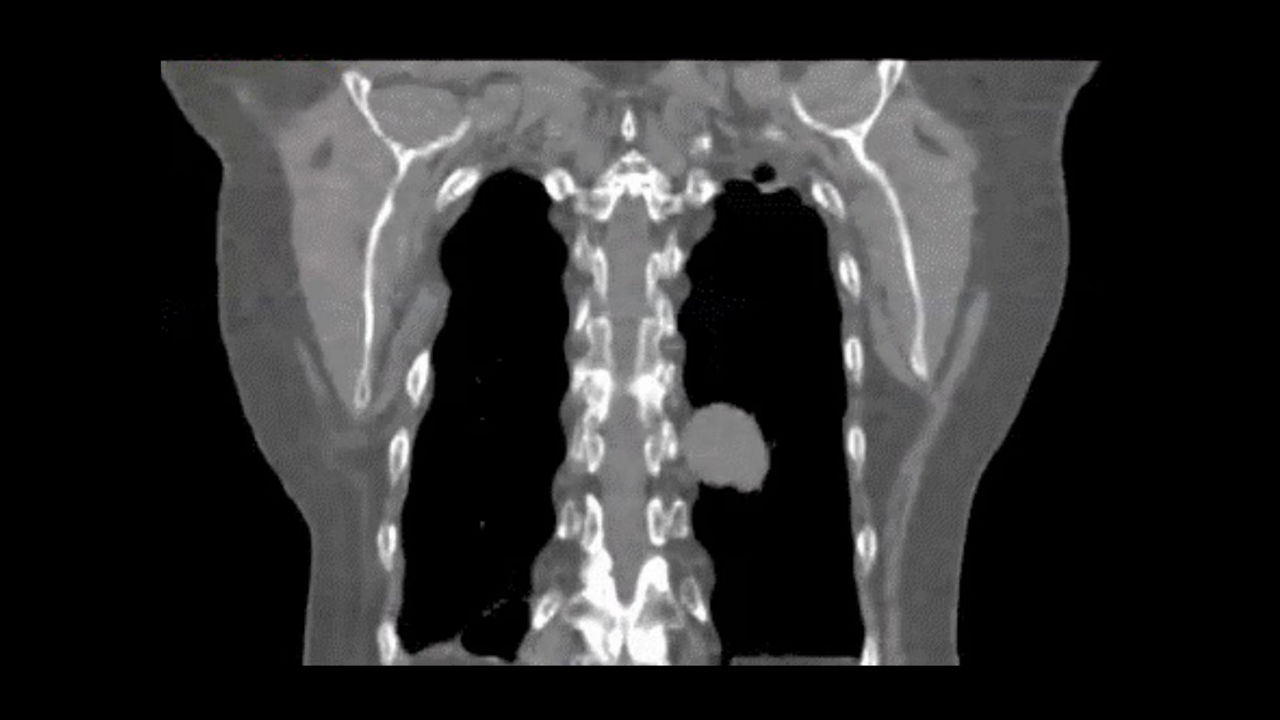

Smart Subscription CT

Smart Subscription is a subscription service that helps you keep pace with clinical and workflow innovations, by providing the latest upgrades and updates to your existing CT capabilities.1

Smart Subscription helps solve the oldest challenge with buying imaging equipment: every time you buy a new system, you’re locked into its capabilities even as new capabilities become available. Smart Subscription helps overcome this challenge by making it possible to keep your CT systems up-to-date.

Smart Subscription includes a broad range of application packages across many different imaging services, giving you the flexibility to choose how you want to expand your CT capabilities.

Everyone starts with the Base Package. Then, you can choose to add additional packages individually or subscribe to the Unlimited Edition for access to all applications. By subscribing to an individual package, you will get access to current capabilities offered within that package, but also any future updates and upgrades1 that will be deployed.